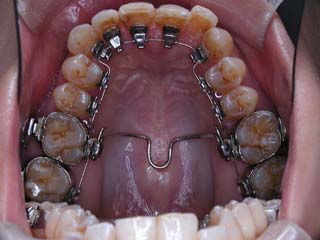

この症例では、上顎にリンガルブラケット矯正装置(Kurz)が用いられています。

歯科矯正用アンカースクリューを用いた矯正治療について、歯科矯正用アンカースクリュー(デュアルトップオートスクリュー、ISAアドバンスなど)は医療機器認証番号がある製品が用いられます。また、オーソアンカー SMAPシステム のように医療機器承認番号があっても「顎顔面変形症及び不正咬合の外科的矯正治療、外科的矯正治療後の顎間固定」用の骨接合用品について、歯科矯正用として用いた場合は薬機法対象外の矯正歯科装置となり、医薬品副作用被害救済制度の対象外となる場合があります。

この症例では、目的外使用のオーソアンカー SMAPシステム が用いられています。

使用した主な装置名:TPB、上顎リンガルブラケット矯正装置、下顎マルチブラケット装置、オーソアンカー SMAPシステム

本症例について検査診断の結果、開咬、叢生、下顎前突傾向を認めました。患者希望を考慮し、治療メカニクスとして、非抜歯配列、上顎のみリンガルブラケット矯正装置、下顎唇側マルチブラケット矯正装置、および、目的外使用のオーソアンカー SMAPシステムを用いることにいたしました。

リンガルブラケットで有れば、内側に歯科矯正用アンカースクリューを装着する方が楽なのですが、この当時は歯科矯正用アンカースクリューの成功率が十分ではない感触があったので、オーソアンカー SMAPシステムを第一選択肢にしていました。今は逆です。場所さえ選べば、歯科矯正用アンカースクリューの成績は決して悪くない上に、装着時の疼痛が極めて少ないことから、第一選択肢を歯科矯正用アンカースクリューにする事が多くなりました。